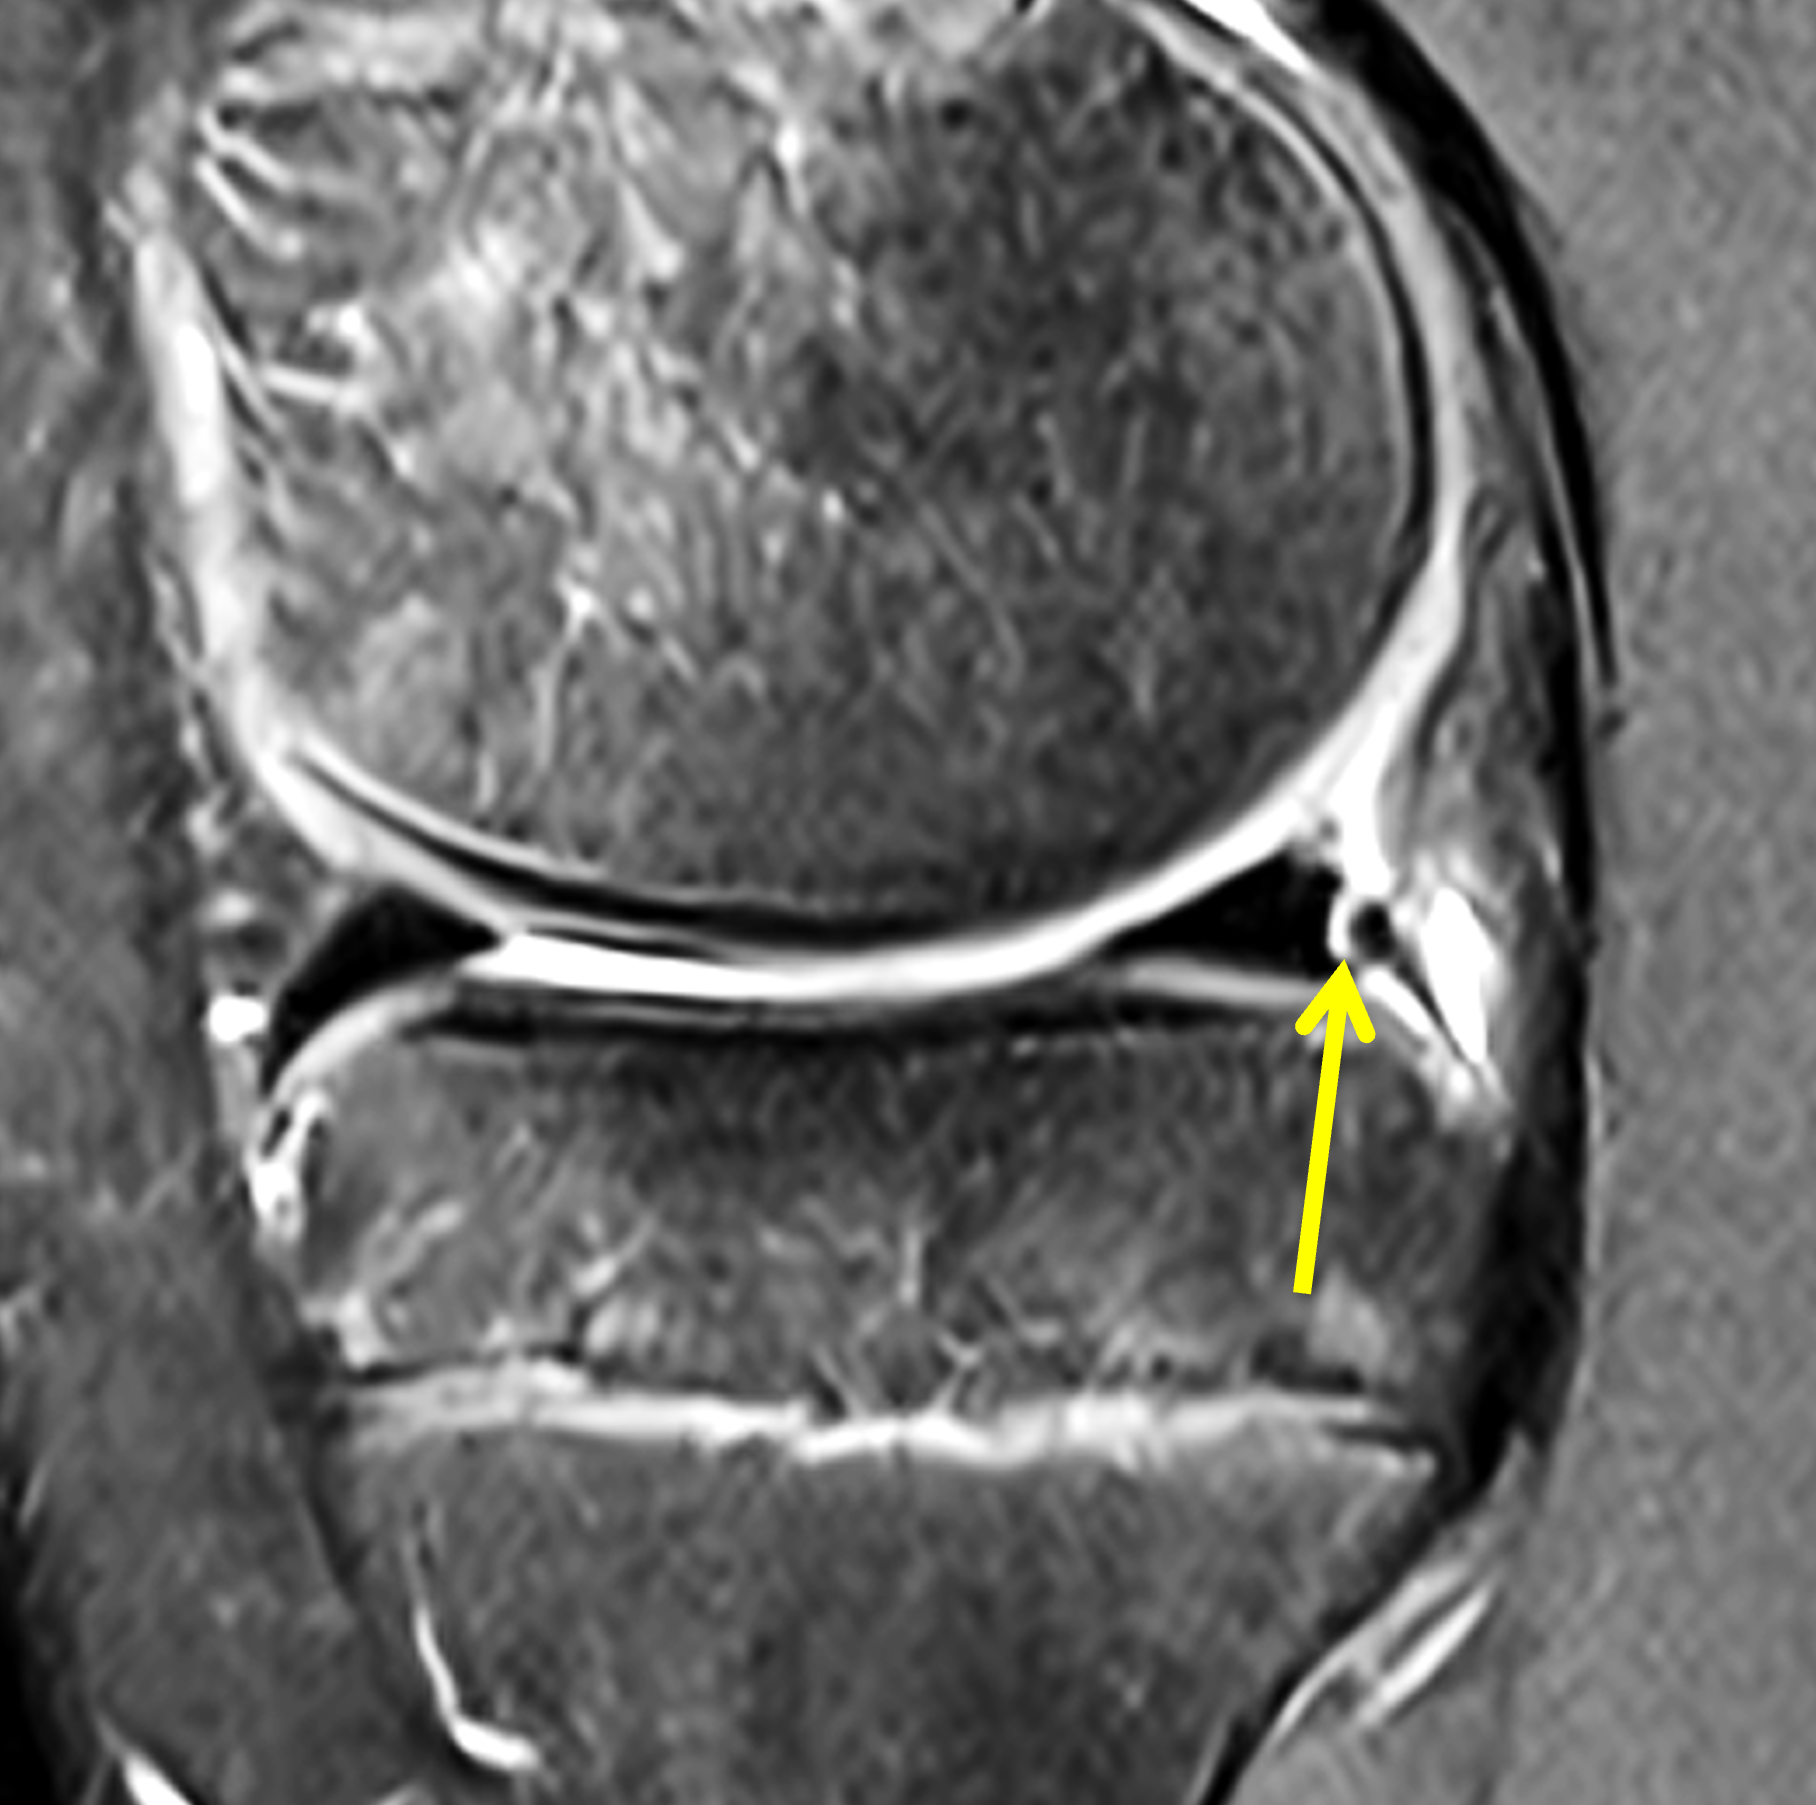

A 19-year-old collegiate baseball player sustained a twisting injury to the knee 3 weeks earlier. Sagittal (1A) proton density-weighted fat-suppressed image through the intercondylar notch, (1B and 1C) proton density-weighted images through the medial compartment, and (1D) fat-suppressed proton density image through the medial compartment are provided. What are the findings? What is your diagnosis?

Figure 2: (2A) Sagittal image through the intercondylar notch shows a complete tear of the anterior cruciate ligament (arrowheads). (2B and 2C) Near the posterior meniscocapsular junction of the medial meniscus, there is disruption of the posterior meniscotibial ligament (red arrow) and irregularity of the posterior meniscocapsular ligament (yellow arrow). (2D) On the fluid-sensitive sequence, linear high signal intensity is interposed between the ligaments and the posterior horn of the medial meniscus (arrowheads).

Anterior cruciate ligament tear with a medial meniscal ramp lesion.